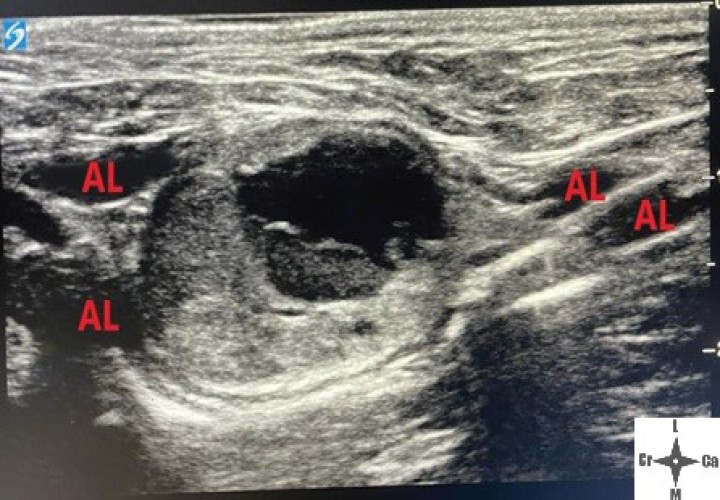

<p>Ventana acústica observando la neoplasia cavitada y la distribución del volumen inyectado (AL).</p>

Ventana acústica observando la neoplasia cavitada y la distribución del volumen inyectado (AL).

Con el fin de evitar el uso de opioides, se planificó una ALO cuya premedicación consistió en dexmedetomidina (Dexmopet, Fatro, Barcelona) 8 µg/kg vía intramuscular, considerando el carácter nervioso y excitable del paciente. A los 15 minutos se canalizó la vena cefálica (Sterican 22G x 1, BBraun vetcare, Barcelona), previa preoxigenación, y la anestesia se indujo con 3,5 mg/kg de propofol intravenoso (IV) (Propofol Lipuro, BBraun Vetcare, Barcelona). El mantenimiento anestésico se realizó con sevoflurano (SevoFlo, Zoetis, Louvain-la-Neuve) (concentración de sevoflurano espirada entre 1,7-2,0) empleando una FiO2 de 0,5 y ventilación espontánea. Se monitorizó la pulsioximetría, temperatura, ECG, capnografía, presión arterial no invasiva (PANI) y espirometría mediante un monitor multiparamétrico (5S Datex-Ohmeda, Finlandia). Se planeó realizar una TC prequirúrgica para volver a valorar la masa antes de comenzar la cirugía. Aprovechando esta circunstancia, se colocó al paciente en decúbito lateral izquierdo, depilando la región cervical, y se procedió a realizar un bloqueo anestésico ecoguiado empleando un ecógrafo portátil (Sonosite M-turbo, Sonosite, EUA) con sonda lineal 10-15 MHz posicionada inmediatamente ventral al ala del atlas en sentido longitudinal a la columna cervical (Figs. 2 y 3). Se localizaron las raíces ventrales cervicales de C2 y C3, las cuales se visualizan en el plano interfascial entre los músculos omotransverso e intertransversos, como engrosamientos de este, siendo dichas raíces estructuras elipsoidales con un halo hiperecoico y su centro hipoecoico. La neoplasia se encontraba próxima al sitio de inyección (Fig. 4). Se realizó un abordaje en plano y se inyectó una mezcla de bupivacaína (Bupivacaine, BBraun, Barcelona) 0,5 % con contraste iodado (Ultravist 300, Berlimed S.A, Alcalá de Henares) en una proporción de 4:1, a razón de 0,15 ml/kg alrededor del espacio interfascial de C2, confirmando la hidrodisección de este plano (Fig. 4). Además, se realizó la inyección contralateral subcutánea en las ramas ventrales superficiales de C2, que se localizan anatómicamente aproximadamente entre 0,5 y 1 cm dorsal a la bifurcación de la vena yugular en la grasa subcutánea profunda al platisma, utilizando 0,1 ml/kg de bupivacaína 0,5 % (Fig. 5). Dichos bloqueos se realizaron tras un exhaustivo estudio de la anatomía de la región, el reconocimiento cadavérico de dichas estructuras y empleando como referencia tanto el bloqueo descrito en equinos como el bloqueo intermedio del plexo cervical descrito en humanos. Se utilizó una aguja espinal (Spinocan Quincke 22 gauge, BBraun, Barcelona). Una vez realizado el bloqueo se repitió inmediatamente otra TC para evaluar la distribución de la solución inyectada (Figs. 6 y 7).